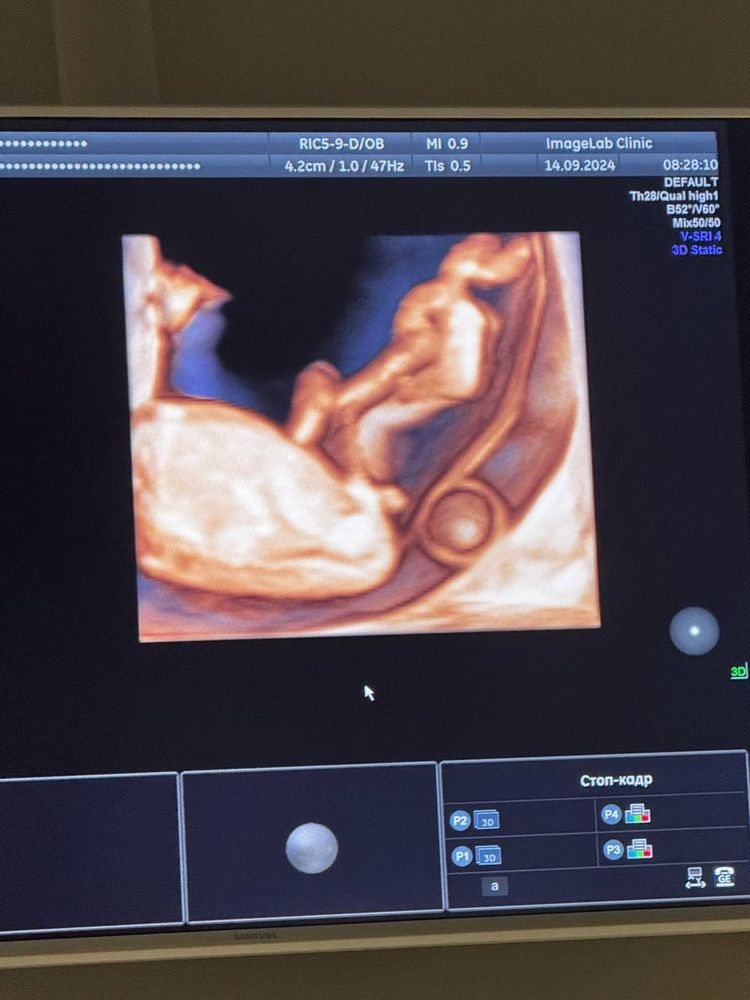

Аннушка Аннушка , мой врач предположила мальчика после того как заглянула 3 д изображением прям где попа под ноги, но тут все пишут девочка, через недельку придет кровь на пол, отпишусь вам)

14.09.2024